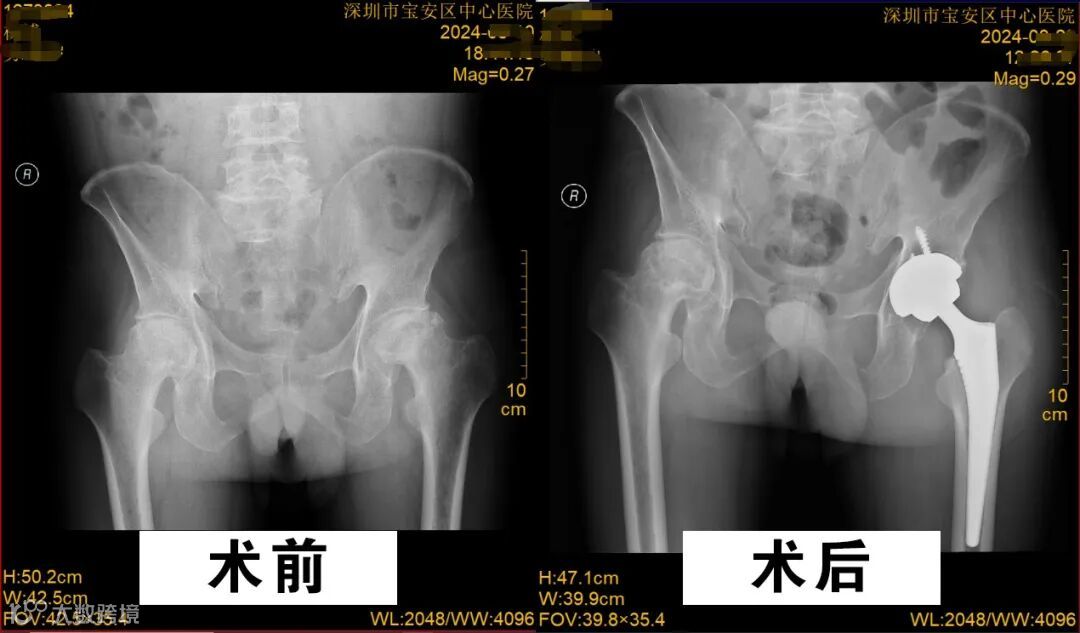

杨先生各项指标在治疗下达到进行手术要求后,麻醉手术科、手术室密切配合,骨关节与运动医学科邓少杰、米浩杰、欧阳鹏医生成功为他实施了右髋关节置换手术。术中杨先生在麻醉科的监控下情况稳定,术中出血少,手术顺利!